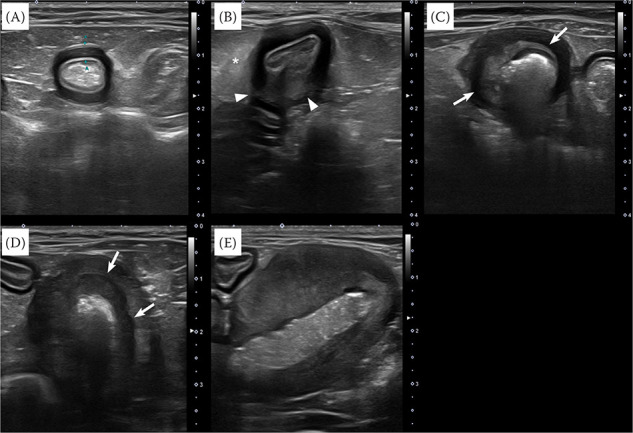

A 6-month-old Ragdoll and 9-year-old Russian Blue cat presented with vomiting. Ultrasonography and computed tomography showed a pyloric antrum mass with wall layering loss and regional lymphadenopathy in the Ragdoll kitten. The Russian Blue cat only presented with muscularis layer thickening throughout the jejunum; however, despite medications, it later progressed to a mass with wall layering loss on the serial ultrasound. Both cats underwent surgery, and feline gastrointestinal eosinophilic sclerosing fibroplasia (FGESF) was histologically confirmed. FGESF should be considered for gastrointestinal masses demonstrating wall layering loss and lymphadenopathy, even in kittens, and intestinal muscularis layer thickening that is refractory to medications.